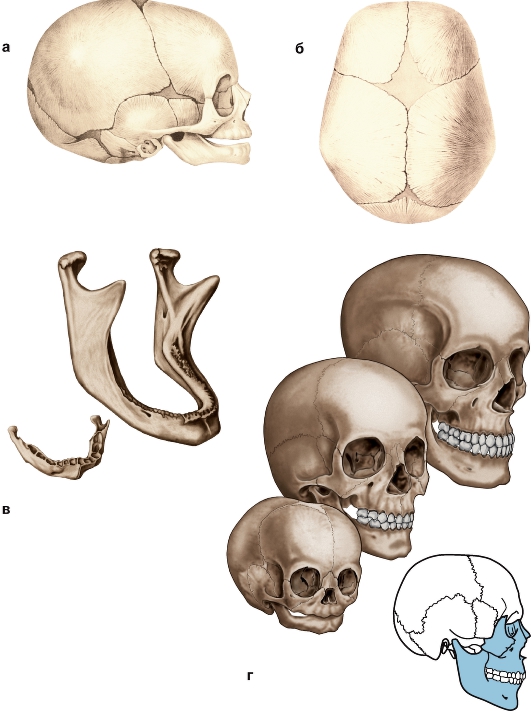

Анатомия детского черепа: Рентгеновские снимки и описание